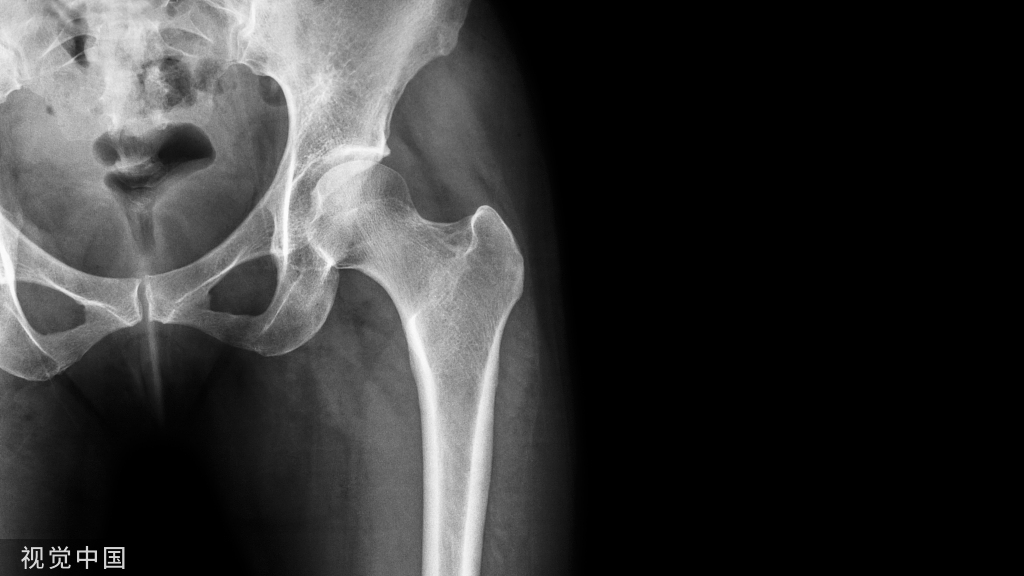

全膝关节置换术(TKA)是目前治疗终末期膝关节疾病的主要方法。TKA术后常伴有中度至重度的疼痛,严重影响患者术后康复、患者满意度和总体疗效。多模式镇痛被认为是缓解TKA术后疼痛的理想方案。目前尚无TKA围手术期疼痛管理指南。经中华医学会骨科学分会关节外科学组、北京医学会骨科专业委员会关节外科学组批准及专家讨论,采用推荐意见的分级评估、制定及评价(GRADE)方法及国际实践指南报告规范(RIGHT),遴选出最为关注的20 个临床问题,通过证据检索、证据质量评价及确立推荐意见和强度,采用德尔菲法进行4 轮函询,最终形成20 条推荐意见。本指南的制定旨在提高TKA围手术期疼痛管理的规范化和标准化。